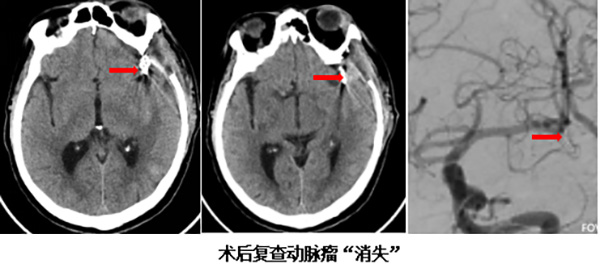

在坚实的后方保障下,神经外科由丁小明主刀,在手术显微镜下展开精细操作。凭借精湛的显微外科技术,团队小心翼翼地分离脑组织,避开重要功能区,最终成功将动脉瘤夹闭,彻底解除了再出血的风险。整个手术过程中,麻醉医生、手术室护士与外科医生三方紧密沟通、默契协作,确保了手术的流畅与安全。